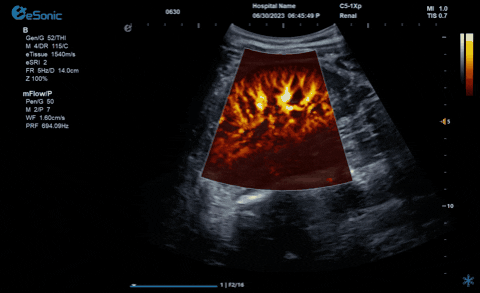

析“微”查异,识“微”见远

银河官网医疗的eHertz系列彩色多谱超声诊断系统凭借强大的RawVision?原数精准平台和SDBeam?软波声束合成技术推出专属的mFlow ?超微血流显像技术,该项技术可专用于极低速血流成像。彩色多普勒血流(CDFI)检查时,通常会将滤波器的频率设置为大约50hz,并随时调整标尺和增益,以便在背景噪声发生前显示小血管......